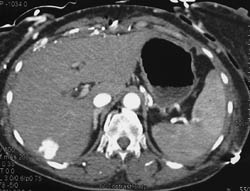

Hepatoma